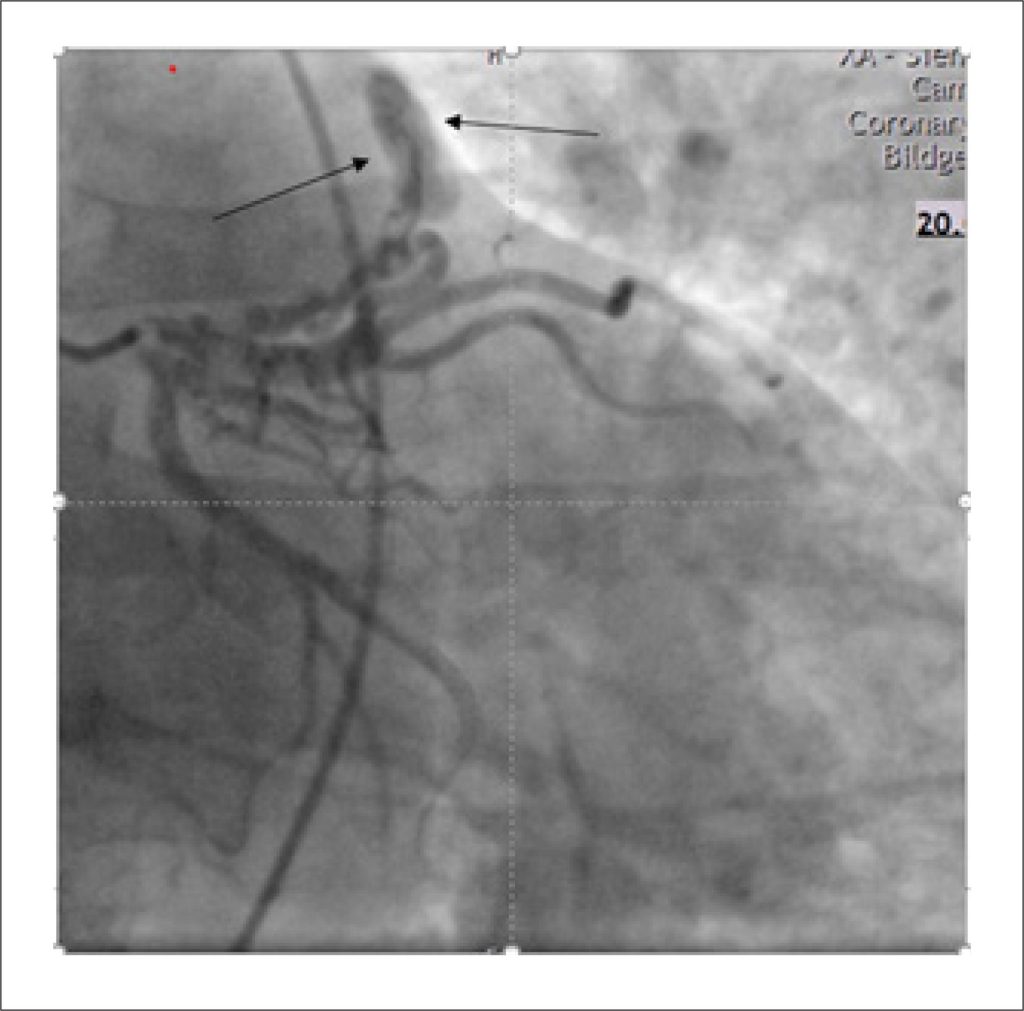

Apresentamos o caso de um homem de 55 anos que apresentou início agudo de dispneia com duração aproximada de duas horas. A avaliação clínica inicial e os exames de rotina – incluindo exame físico, ecocardiografia, eletrocardiografia e cateterismo cardíaco direito e esquerdo – levantaram suspeita de uma anomalia cardíaca subjacente, motivando investigação adicional. A subsequente Ressonância Magnética Cardíaca (RMC) e a Tomografia Computadorizada Multidetector (TCMD) revelaram a presença de uma Conexão Venosa Pulmonar Anômala Parcial acompanhada de FACs. Dadas as características não complexas do shunt neste caso, foi tomada uma decisão compartilhada com o paciente de prosseguir com tratamento conservador.